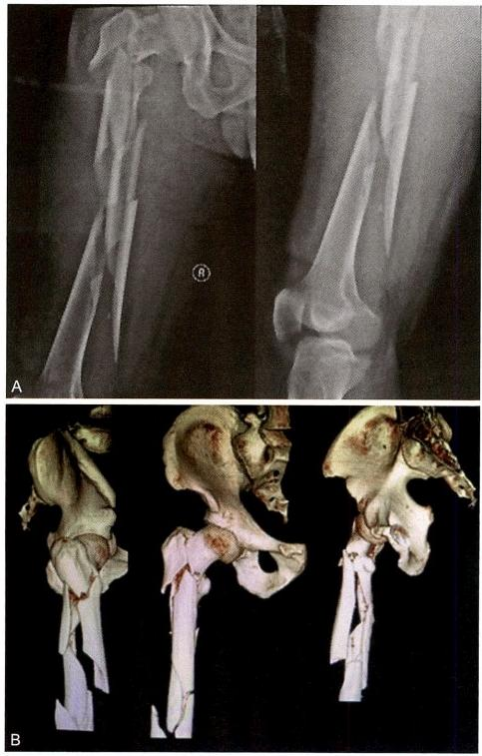

患者为严重粉碎性骨折,股骨转子下+中段骨折,LambirisⅡ 型 ( 图 12-2)。

图12-2 严重粉碎性骨折,股骨转子下+中段骨折,LambirisⅡ型

股骨多段骨折,伴股骨转子间、转子下骨折,LambirisⅡ 型(图12-8)。

图12-8 股骨干多段骨折伴股骨转子间、转子下骨折,Lambiris Ⅱ型。A.术前X 线片;B.术前三维CT